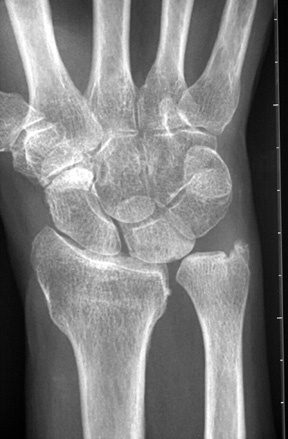

Diagnosis? Etiology?

Keinbochs

Diagnosis? Classification

Keinboch’s - Litchman Classification

What conditions are associated with the pathological finding of this XR? What would you expect to find on physical exam?

Ulnar Positive Variance

What conditions are associated with the pathological finding of this XR?

Ulnar Negative Variance